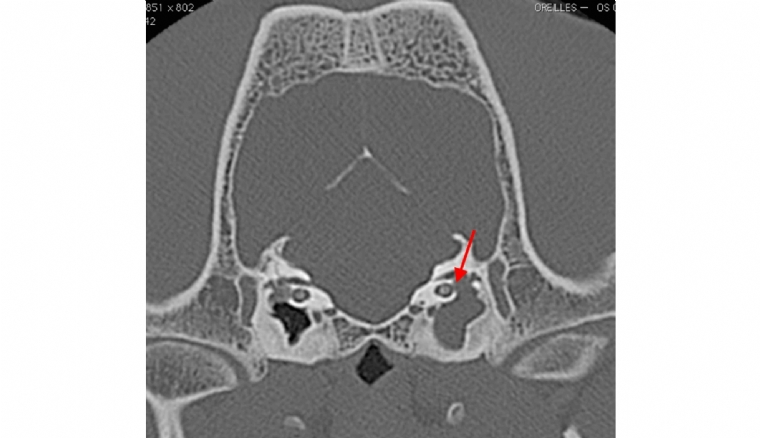

Mercredi 30 Mars 2022 Animaux de compagniePhoto n° 1 : Coupe tomodensitométrique transverse du crâne d'un bouledogue français présentant une otite moyenne et interne unilatéralement à gauche (flèche).